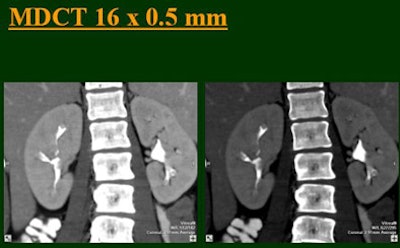

"As we've been scanning through the kidneys, we've been noticing that there has been an increase in the quality images as we go from (single-) to four-, eight-, and 16-row detector scans," Raptopoulos said. "Our purpose, then, was to assess the quality of CTU with progressively improving CT technology from (single-) to 4-, 8-, and 16-row scanners, using a split-injection single scanning technique."

| Top to bottom: Split-bolus CTU improves significantly using a nearly identical protocol but with the addition of more detector rows, from single- (spiral), four-, eight-, and 16-row scanners. All images courtesy of Dr. Vassilios Raptopoulos. |

The single-row scanner required two breath-holds; the other scanners reduced scan time from about 20 seconds (four-slice) down to seven seconds (16-slice). Collimation for the single-row scanner was 5 mm, with 3-mm overlapping reconstructions. Collimation for the four-, eight-, and 16-row scanners was 2.5 mm, 1.5 mm, and 0.5 mm, respectively, with the patients scanned in a prone position.

Based on multiplanar reformatted (MPR) images, there was significant upscale improvement in calyceal detail from the isotropic images provided by single-detector scanning (median score 2) to four- (median score 3), eight- (median score 4), and 16-detector scanning, Raptopoulos said. On MPR images the calyceal were 1, 2, 3, and 5, respectively. The median ureteral filling was 4 for the upper and left-lower ureters, and 3 for the right-lower ureters.

"We're using this technique of biphasic injections not only in CTU, but in general abdominal scanning in trauma, in renal CT, and we can see the renal vessels quite well in relation to the collecting systems," Raptopoulos said. "Combined excretory- and parenchymal-phase CTU is a practical technique, allowing a decrease in patient scanning," he said. "Sixteen-row CTU with the patient in a prone position significantly improves the quality of the exam."